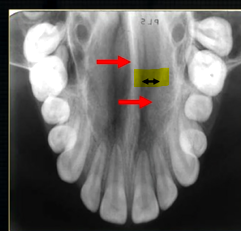

what does this anterior periapical graph show?

oval radiolucent area between the central incisors - is it Infront of the teeth (buccally?) or is it behind them? - you can’t tell radiographically

but its shape and position is compatible with the palatally positioned with the nasopalatine formaina

more posteriorly - radiopacities indicate the nasal septum and floor of the nose

dense, thin , white line in the middle of the image is the nasal septum

less dense opacity is caused by the

inferior nasal concha

radiolucency - nasal septum

lateral wall of the nose

maxillary air sinus

mid-palatal suture

this increased radiopacity is caused by the soft tissues at the tip of the nose - shadow - dense tissue